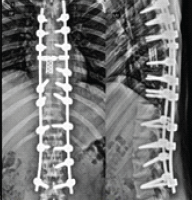

A 40-year-old male with a history of psoriasis and a recent diagnosis of ADHD presented 1 month after initiating Adderall with complaints of calf pain, swelling, and ecchymosis. The patient was prescribed 20 mg Adderall XR (extended release) twice daily for management of his ADHD. He was on medication for 1 month before experiencing severe, sustained muscle spasms in his lower extremity that woke him from sleep and lasted approximately 15 min. The following day, he experienced worsening calf pain, swelling, and ecchymosis along the medial calf (Fig. 1).

Figure 1: Clinical photograph of the posteromedial calf demonstrating significant ecchymosis following injury.

Calf pain was found to be worse with ankle dorsiflexion, particularly when his knee was extended. He presented to the emergency department, where a deep vein thrombosis (DVT) ultrasound was performed and negative for thrombus. While he had significant calf tenderness and stretch pain, compartment syndrome was ruled out, and he was discharged with outpatient referral to orthopedics. In the office, his pain, swelling, and ecchymosis were found to be improving. He had pain with direct pressure over the medial head of his gastrocnemius. The Thompson test was negative for Achilles rupture. Based on clinical examination, he was diagnosed with a tear of the medial head of his gastrocnemius. Treatment consisted of conservative measures with activity modification, ice, elevation, and anti-inflammatories. His Adderall was discontinued. At the time of initial presentation, the patient also had complaints of burning in the bilateral triceps at the distal insertion. He denied any strenuous activity in the days leading up to his injury and had never experienced these symptoms before. His pre-injury activity level was low-moderate. While in the emergency department, his laboratory markers were unremarkable, ruling out dehydration or electrolyte imbalance as a potential cause for his muscle spasms. In addition to recent Adderall use, his only other medications included Zoryve (roflumilast) creame 0.3% and clobetasol scalp foam, which he had been taking for the past several years for his psoriasis. He denied any tobacco use and had a BMI of 43.5.